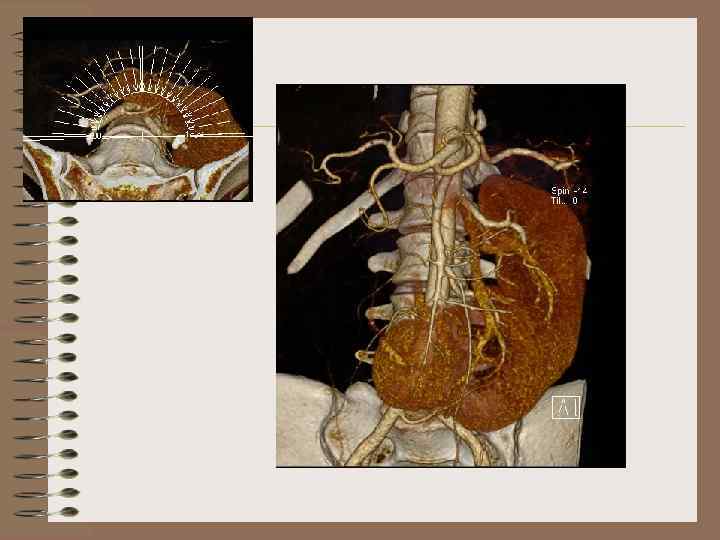

L -образная почка • Одна почка в обычном месте, вторая сращена с ней под прямым углом

L- образная почка • Левая почка перемещена вправо • Сращение нижнего полюса правой почки и нижнемедиальной поверхности левой почки

L- образная почка. МКБ